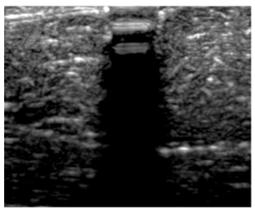

Figure 3.

(a) Selection of ROI-1 and ROI-2 in the B-mode image of the muscle without implants. (b) Selection of ROI-3 and ROI-4 in the B-mode image with aerogel implants.